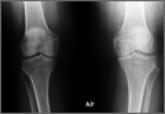

Patient-Directed Valgus Stress Radiograph of the Knee: A New and Novel Technique

The radiographic investigation of patients with medial-compartment osteoarthritis of the knee is a critical element in the decision-making process...